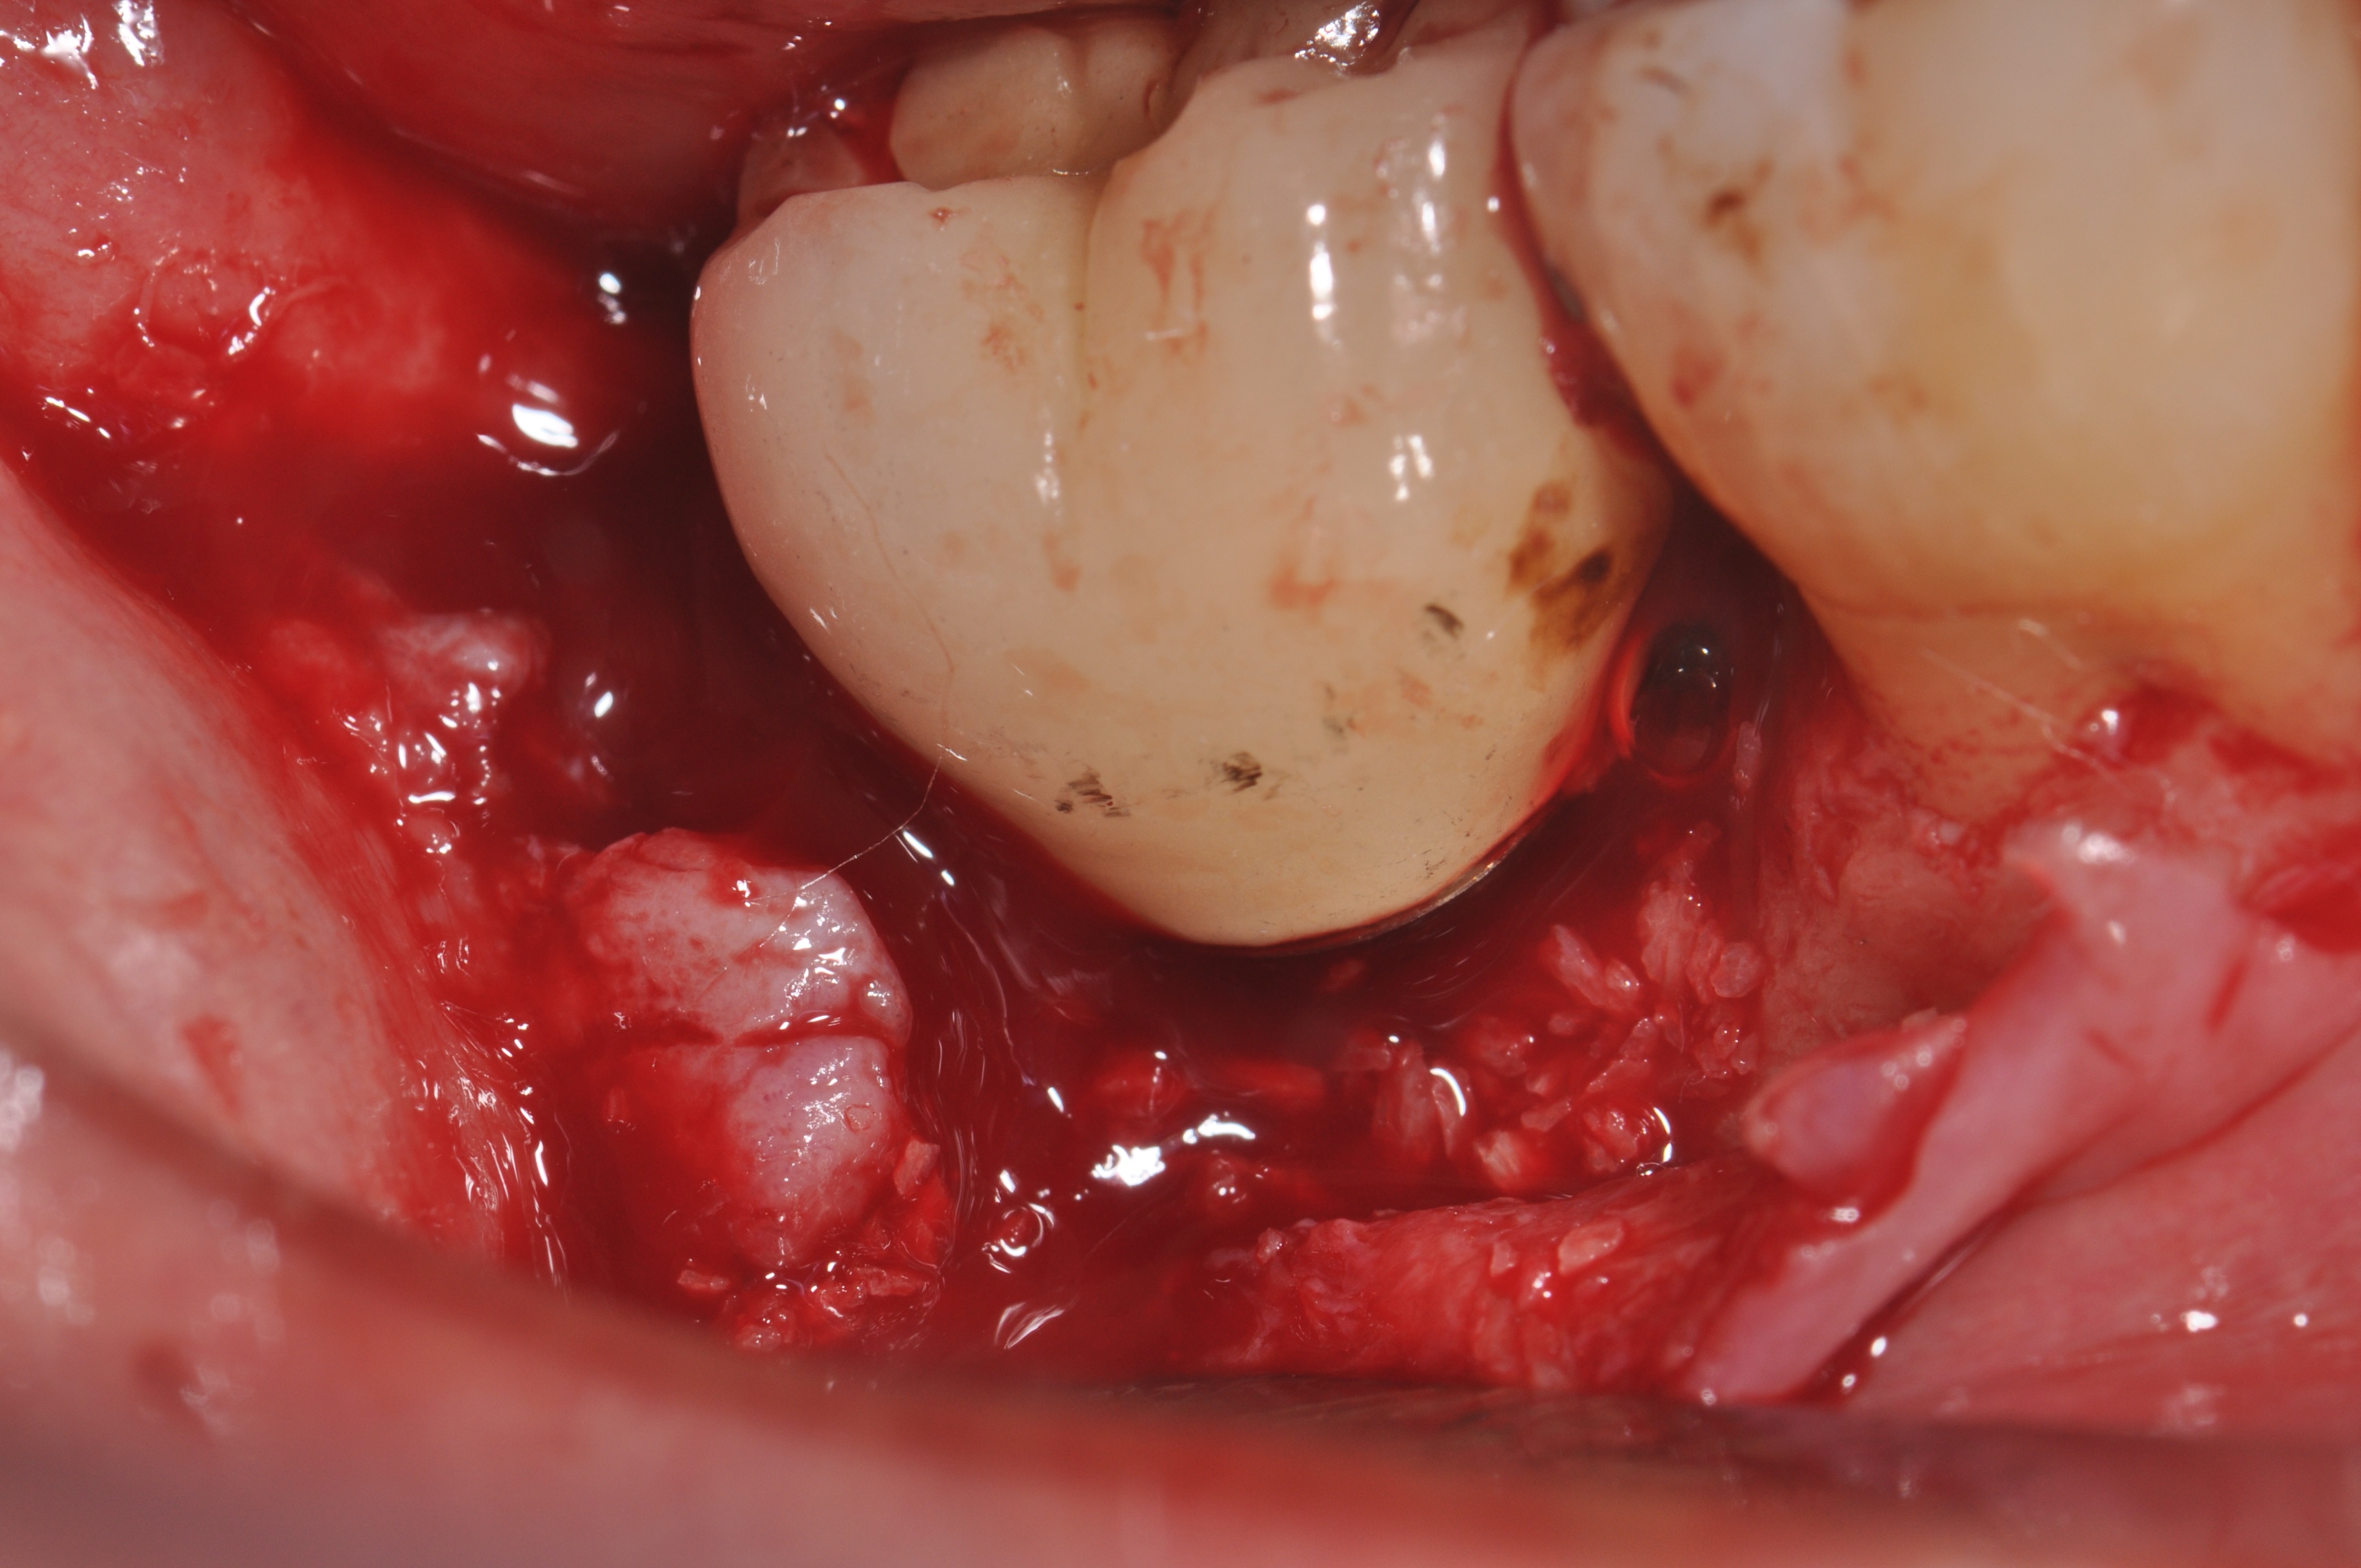

Clinical exposure of a circumferential lesion that demonstrates 3 mm of bone loss. No cement was present, suggesting that the lesion was of bacterial origin. Surface decontamination included citric acid.

Figure 2

The surface of the implant had recombinant platelet-derived growth factor-BB applied after thorough rinsing of the citric acid and a composite graft of mineralized freeze-dried bone mixed with the PDGF-BB and enamel matrix derivative.

Figure 3